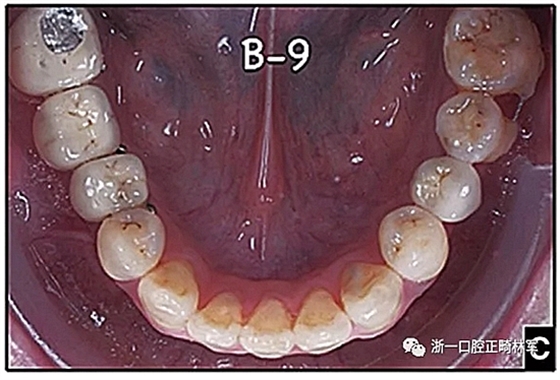

圖15.A,去除固定裝置一個月后,下頜左側第二前磨牙復發(fā),移動到種植體愈合的部位; B,B-0表示開始再治療,通過鏈圈和推簧的矯正復發(fā); C,B-9是治療結束后3個月回訪時下頜弓的咬合面觀,這是再治療階段的9個月。下頜左側第二前磨牙和第三磨牙的頰面粘合一個固定保持器,以防止復發(fā)。